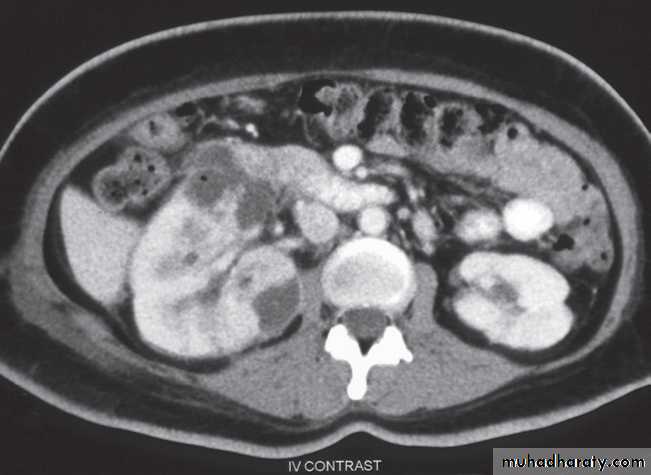

-Angiomyolipomas are usually incidental findings. They are benign tumours, which rarely cause problems, although, on occasion, they cause significant retroperitoneal haemorrhage.

At CT their fat content allows a confident diagnosis (Fig. 8.32b, c).